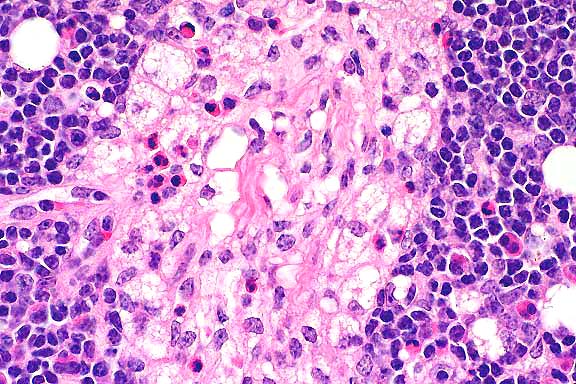

- Case 11-2. Lymph Node. Foamy histiocytic cells efface

and replace normal nodal architecture.

40x

obj

- Case 11-2. Lymph node. Foamy macrophages replace lymphoid

cells. Rare neutrophils and eosinophils are also present.

- AFIP Diagnosis: Lymph node: Histiocytosis, diffuse,

moderate, with intrahistiocytic vacuoles, Salers crossbred calf,

bovine.